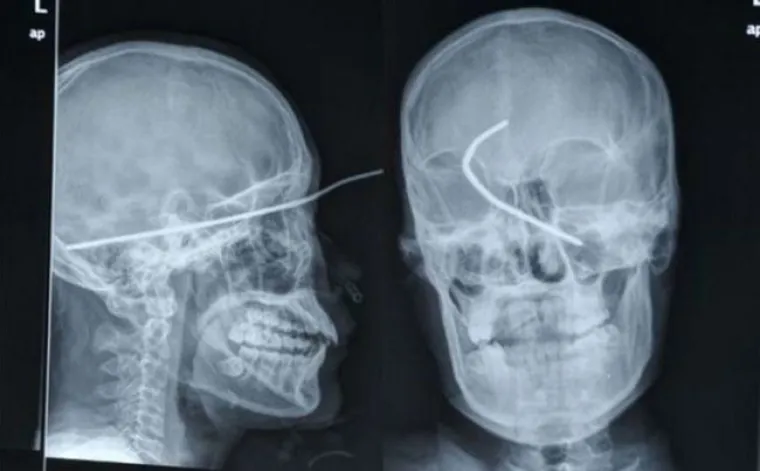

BOLJET ĆE VAS OD SAMOG POGLEDA... Rengenske snimke od kojih će vas proći trnci

Žica u glavi